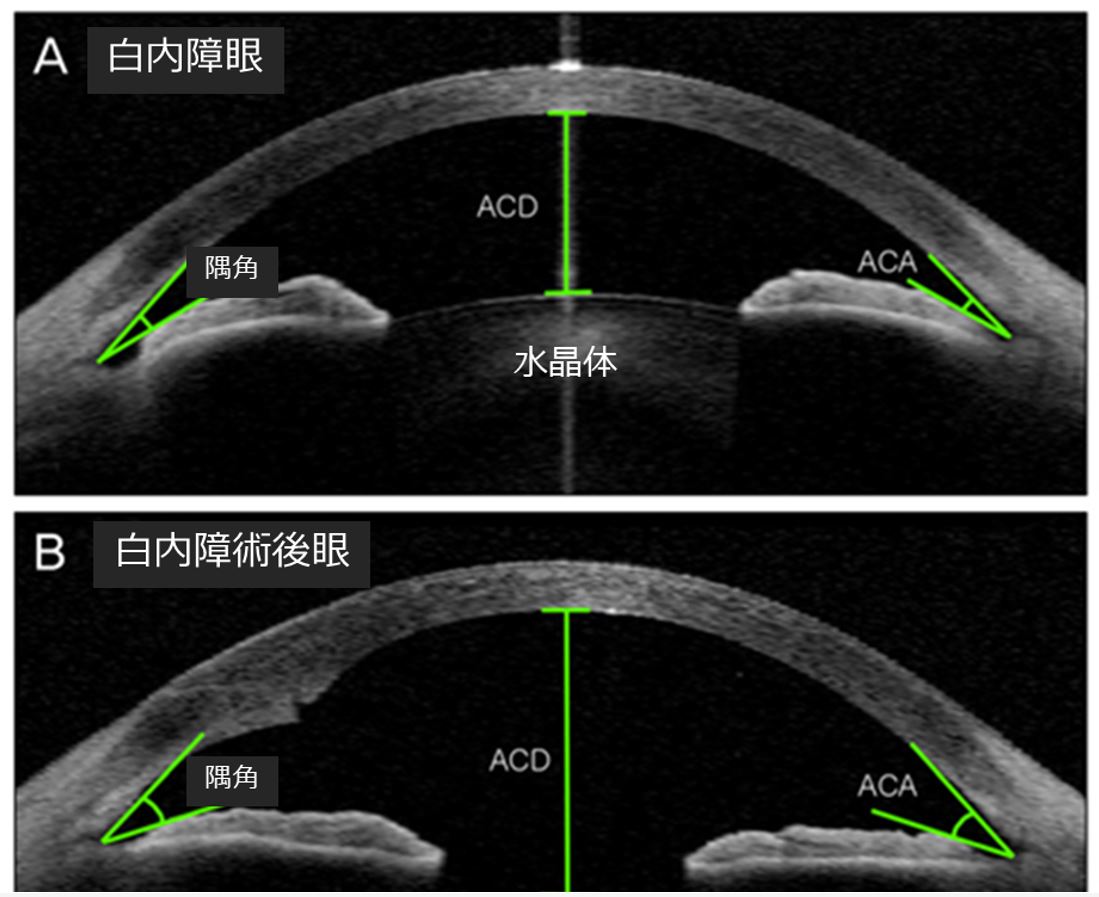

原発性閉塞隅角緑内障では、目の構造により虹彩が線維柱帯に押し付けられる可能性が高くなります。これは次の理由が考えられます。

- 虹彩と角膜の間の角度は非常に狭い

- 眼球は前から後ろに測ると比較的短いです

- 目の中の水晶体が厚く、虹彩が前方に押し出される

閉塞隅角緑内障の治療

閉塞隅角緑内障の治療には、薬物療法と手術が使用されます。

眼圧が低下したら、再び眼圧が上昇するのを防ぐためのさらなる治療が必要になります。閉塞隅角緑内障に対処するために使用される手術は 2 つあります。

- 周囲虹彩切開術。これは虹彩に小さな排水穴を開けるレーザー治療です。急性および慢性両方の閉塞隅角緑内障の治療に使用されます。

- 外科的虹彩切除術。このあまり一般的ではない治療法では、外科医は虹彩に小さな三角形の穴を開けます。